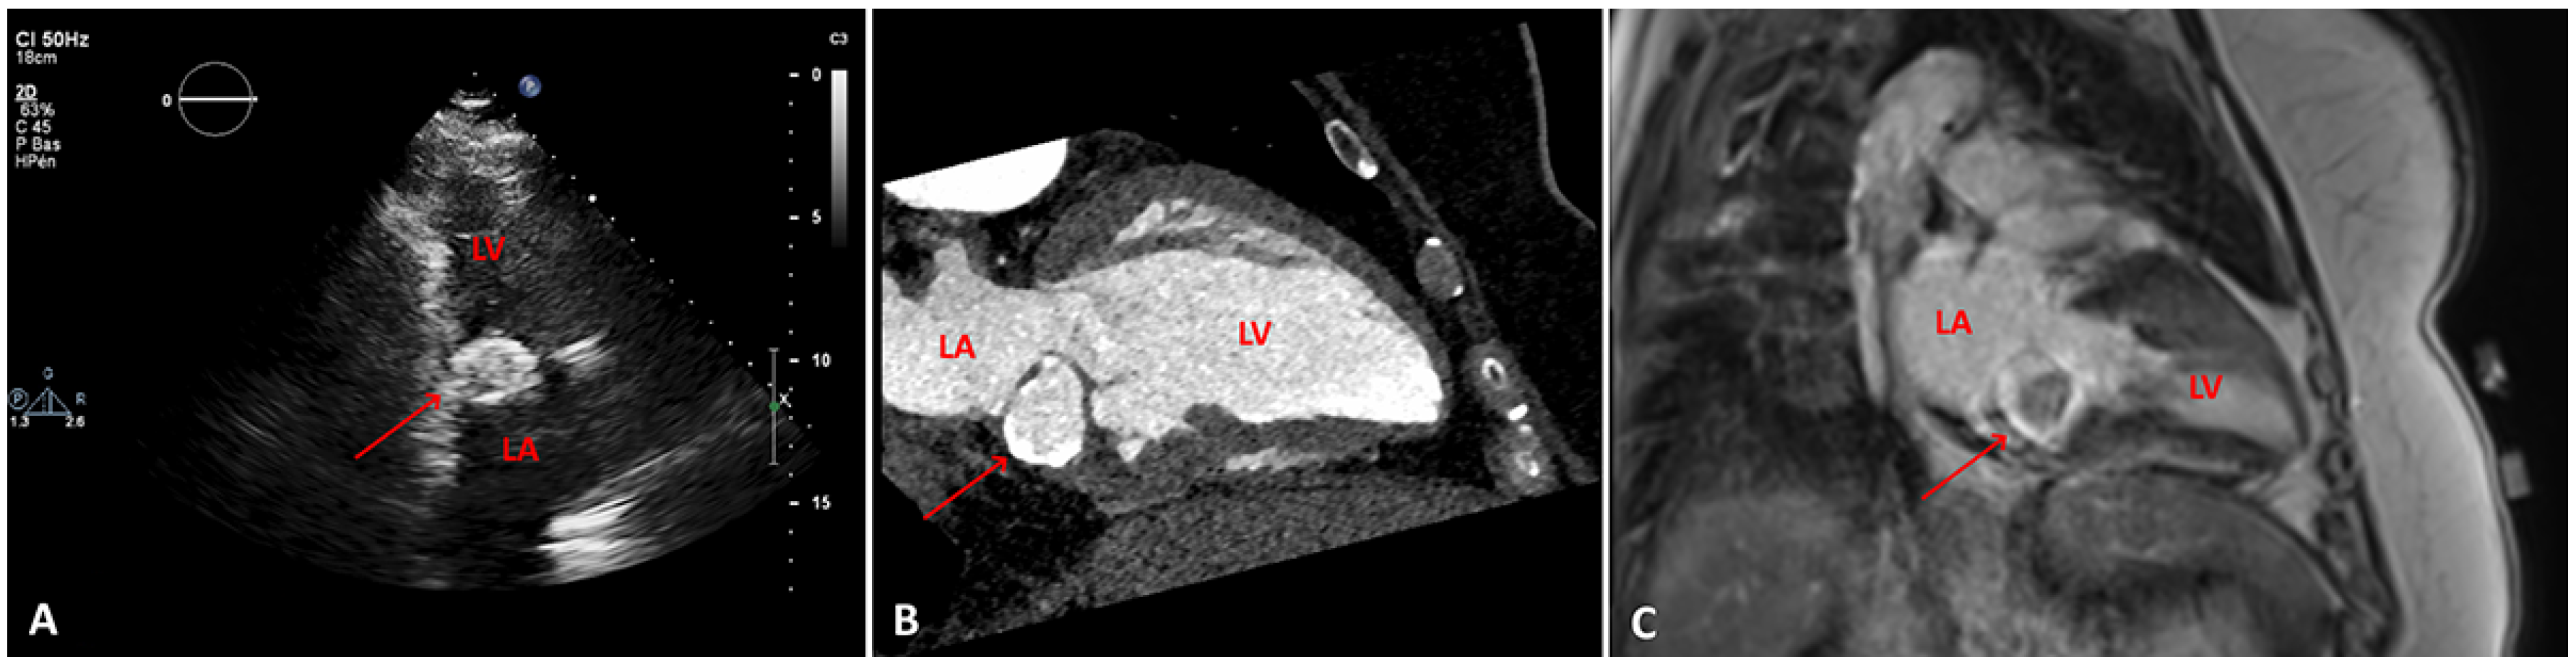

Figure 1. A. transthoracic echocardiogram, two-chamber view showing a posterior mitral annulus caseous calcification (arrow), which appears as a well-defined brightened edge corresponding to an echodense periphery, and a central echolucent area corresponding to the central liquefaction. B. Computed tomography scan, showing a well-defined oval or crescent-shaped hyperdense mass with peripheral calcification (arrow). C. Late gadolinium enhancement-magnetic resonance imaging sequence, showing caseous calcification of the mitral annulus as a hypointense zone without late gadolinium enhancement (arrow). LV: left ventricle; LA: left atrium

A routine transthoracic echocardiogram (TTE) performed 4 years previously, with a view to orthopaedic surgery, had revealed a cardiac mass attached to the posterior mitral annulus with a mitral mean gradient of 6 mm Hg (at a heart rate of 80 beats per minute). At that time cardiac magnetic resonance imaging (cMRI) and computed tomography (CT) were performed and the diagnosis of caseous calcification of the mitral annulus was established (Figure 1). Two years after the initial diagnosis, the patient developed third degree atrioventricular block for which a dual-chamber pacemaker was implanted. The patient was asymptomatic for a further 2 years until she developed an episode of acute severe dyspnoea.

On CT scan, appears as a well-defined oval or crescentshaped hyperdense mass with peripheral calcification, with high Hounsfield units and lack of contrast enhancement [1,7,8].

Cardiac MRI may be helpful in equivocal cases. CCMA is seen as a hypointense zone both in T1- and T2-weighted sequences. In postcontrast studies, contrast enhancement on first-pass sequences is not found; however, there may be peripheral enhancement during delayed postcontrast sequences [7,9,10].